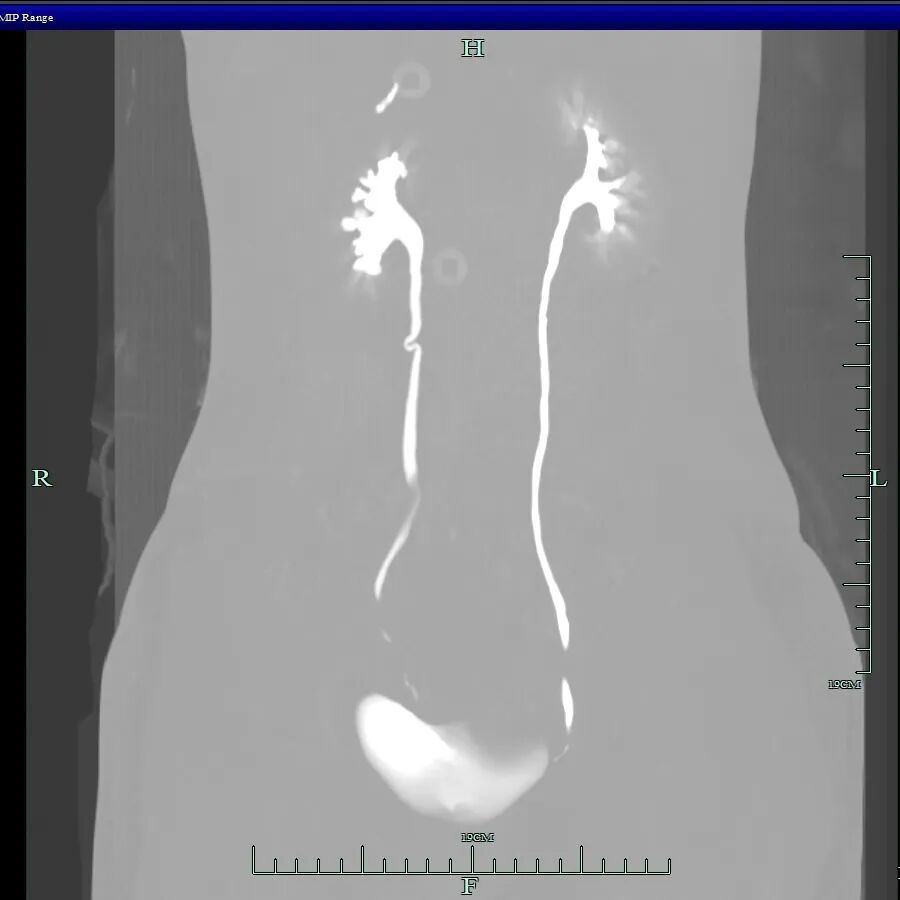

术中发现其盆腔内器官广泛严重粘连,右侧卵巢有直径约10厘米的囊肿,左侧卵巢亦有囊肿,并在直肠前壁等多处发现异位病灶。手术团队凭借精湛技术成功分离粘连,精准切除了所有病灶,并修复受损组织,保住了生育器官,手术圆满完成。

· 侵犯器官:异位内膜可深入侵犯肠道、膀胱、输尿管,引起便血、便秘、尿血、肾积水等严重并发症,正如小杨所遭遇的一样。